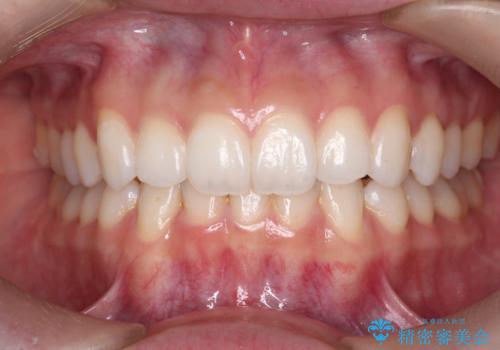

歯を抜かずに後方移動で達成する、前突感の改善

マイクロインプラントを用いてしっかりと後方移動を行ったことで前歯の角度は改善され、口元もすっきりと仕上げることができました。